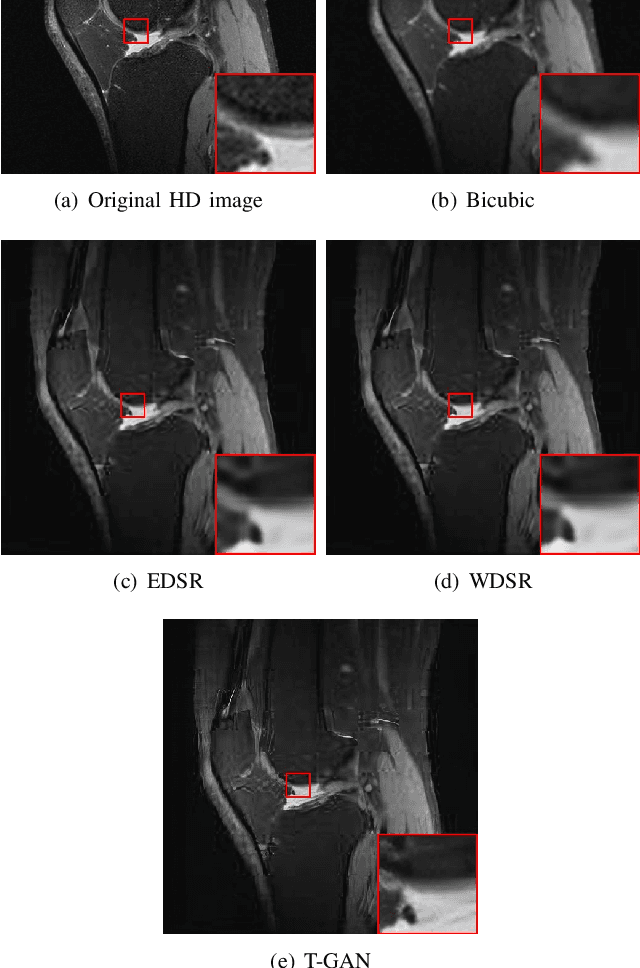

Abstract:Because of the necessity to obtain high-quality images with minimal radiation doses, such as in low-field magnetic resonance imaging, super-resolution reconstruction in medical imaging has become more popular (MRI). However, due to the complexity and high aesthetic requirements of medical imaging, image super-resolution reconstruction remains a difficult challenge. In this paper, we offer a deep learning-based strategy for reconstructing medical images from low resolutions utilizing Transformer and Generative Adversarial Networks (T-GAN). The integrated system can extract more precise texture information and focus more on important locations through global image matching after successfully inserting Transformer into the generative adversarial network for picture reconstruction. Furthermore, we weighted the combination of content loss, adversarial loss, and adversarial feature loss as the final multi-task loss function during the training of our proposed model T-GAN. In comparison to established measures like PSNR and SSIM, our suggested T-GAN achieves optimal performance and recovers more texture features in super-resolution reconstruction of MRI scanned images of the knees and belly.